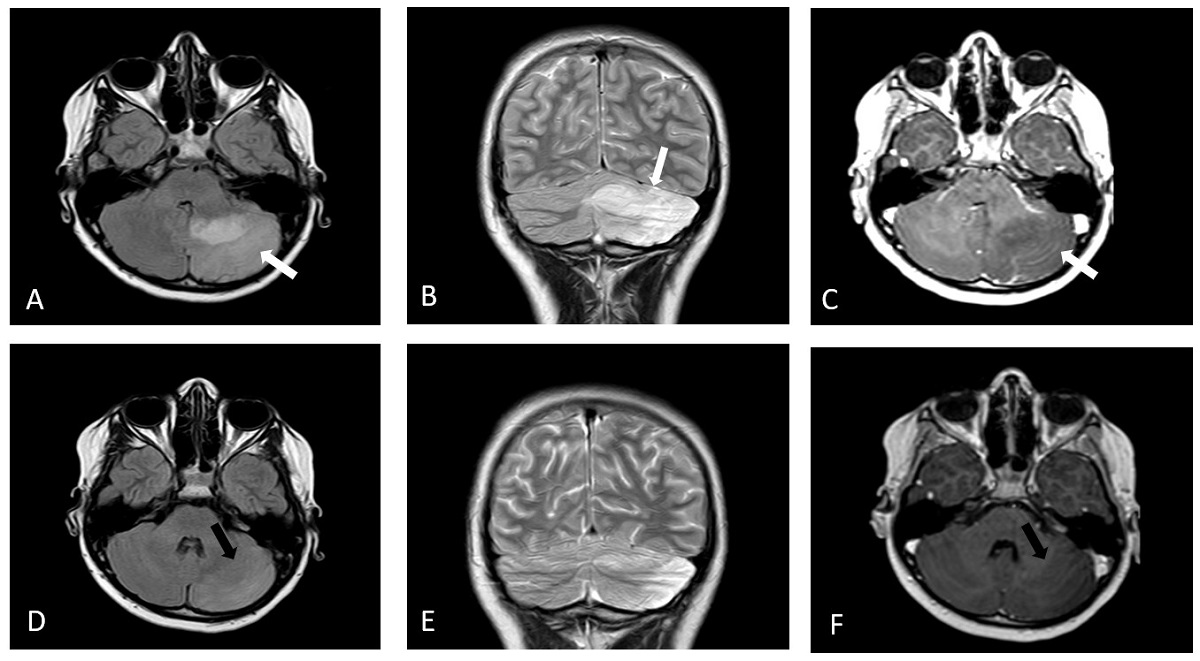

| Figura 2. Cerebelitis aguda. Evolución de la afectación cerebelosa en el caso 1. Control a los 8 meses: (A) Axial FLAIR. (B) Coronal FSE T2. (C) Axial eco de gradiente T1 con contraste. Secuela de cerebelitis con encefalomacia de hemisferio cerebeloso izquierdo que presenta ampliación del espacio subaracnoideo y gliosis sin realce tras contraste (flechas blancas). Control a los 4 años. (D) Axial FLAIR. (E) Coronal FSE T2. Leve aumento de la encefalomalacia de hemisferio cerebeloso izquierdo con gliosis y mayor ampliación del espacio subaracnoideo (flechas negras). Caso 2: (F). Difusión. RM difusión, proyección axial. Hiperintensidad difusa del cerebelo sólo en la fase aguda de la cerebelitis. |

Varón de 6 años, sin antecedentes personales ni familiares de interés. 15 días tras una varicela, ingresó por fiebre, rigidez cervical y disartria. La exploración neurológica mostraba un síndrome cerebeloso con ataxia marcada. La RM mostró una difusión anormal (Fig. 2F) con secuencias T1, T2 y FLAIR sin hallazgos. El enfermo mejoró rápidamente y la RM era normal al mes del alta y en controles posteriores en todas las secuencias. A pesar de una buena recuperación del habla, aparecen síntomas de inatención e impulsividad, así como un comportamiento disruptivo ante tareas propias de su edad. Los padres le observan 'abatido', 'cansado' y “sin iniciativa para socializarse”. Con 7 años la evaluación neuropsicológica demuestra afectación atencional severa, velocidad de procesamiento lenta, dificultades visoperceptivas y baja fluencia verbal. El tratamiento con metilfenidato empeora los comportamientos disruptivos. Tras dos meses de fluoxetina es posible incorporar de nuevo metilfenidato, pero aún, de forma menos acusada, persiste irritabilidad. El tratamiento con lisdexanfetamina de 30 mg mejora la conducta y permite realizar las tareas con mayor rapidez, por lo que se mantiene con el mismo hasta ahora. Un año después se retira fluoxetina sin problemas.